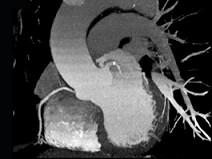

上面一组图像考虑为 ( )A、左前降支钙化B、左旋支钙化C、正常的左前降支D、右侧冠状动脉钙化E、正常的右侧冠状动脉

问题 上面一组图像考虑为 ( )

选项 A、左前降支钙化 B、左旋支钙化 C、正常的左前降支 D、右侧冠状动脉钙化 E、正常的右侧冠状动脉

答案 A